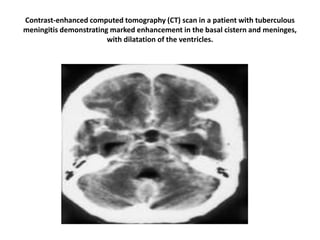

Contrast-enhanced computed tomography (CT) scan in a patient with tuberculous

meningitis demonstrating marked enhancement in the basal cistern and meninges,

with dilatation of the ventricles.

Contrast-enhanced computed tomography(CT) scan in a patient with tuberculous meningitis demonstrating marked enhancement in the basal cistern and meninges, with dilatation of the ventricles.